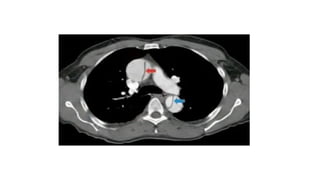

• Angio-TC toracoabdominal: la técnica diagnóstica de elección para

diagnostico y planificar una eventual cirugía

- No se puede realizar en pacientes hemodinámicamente inestables con

hipotensión grave y mala perfusión periférica

Diagnóstico • Radiografía detórax. Es la primera prueba que se debe realizar ante la sospecha clínica. Típicamente se objetivará un ensanchamiento mediastínico (60%) • ECG: disección se extiende hacia las arterias coronarias puede aparecer elevación del ST.

• Angio-TC toracoabdominal:la técnica diagnóstica de elección para diagnostico y planificar una eventual cirugía - No se puede realizar en pacientes hemodinámicamente inestables con hipotensión grave y mala perfusión periférica